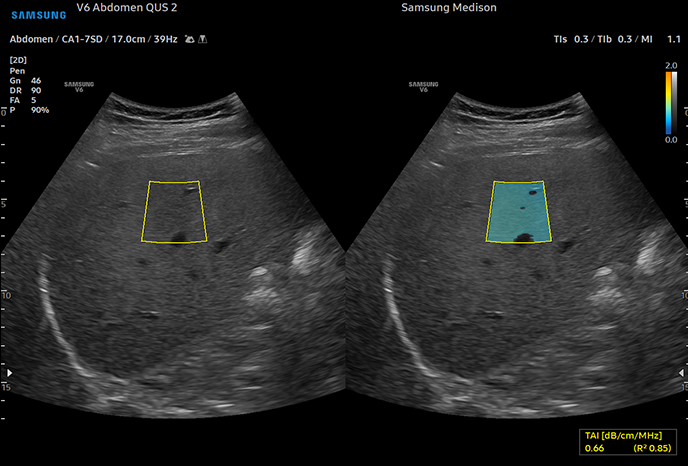

Samsung V6 Ultrasonic

이미지 해상도 극대화, 노이즈 최소화로 장기의 경계부를 선명하게 관찰

조직 자기영상(TAI)